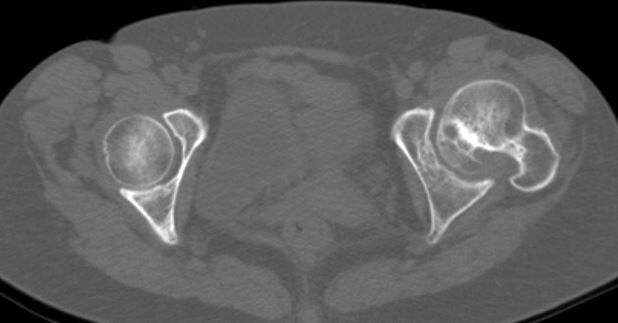

しかし、術前CTで寛骨臼の前方開角が45度、大腿骨頚部前捻角が40度でした...。大腿骨頚部前捻角はまだしも、寛骨臼前方開角は看過できません。

このままの角度でカップを設置すると前方脱臼する可能性があります。しかし、前方開角を減じるとカップ前方で腸腰筋との Irritationを併発して股関節痛を残す原因となりそうです。

かなり検討したのですが、結局カップの前方開角度は通常の症例と同様に20度に減捻して、腸腰筋の Irritationにはある程度目をつぶることしました。

大腿骨にも過大前捻があり、関節不安定性がどうなるのか予測できなかったため、S-ROM-Aでこちらも20度減捻しました。